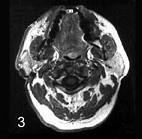

问题 女性,55岁。右耳垂下无痛性肿块逐渐缓慢长大6年。触诊肿块界线清楚,活动,约4cm×5cm大小,表面呈结节状,中等硬度,与皮肤无黏连。

选项 CT 检查结果如图,该病最可能的诊断是 ( ) A.皮脂腺囊肿 B.腮腺腺淋巴瘤 C.腮腺多形性腺瘤 D.耳下淋巴结转移癌 E.慢性淋巴结炎

答案 C